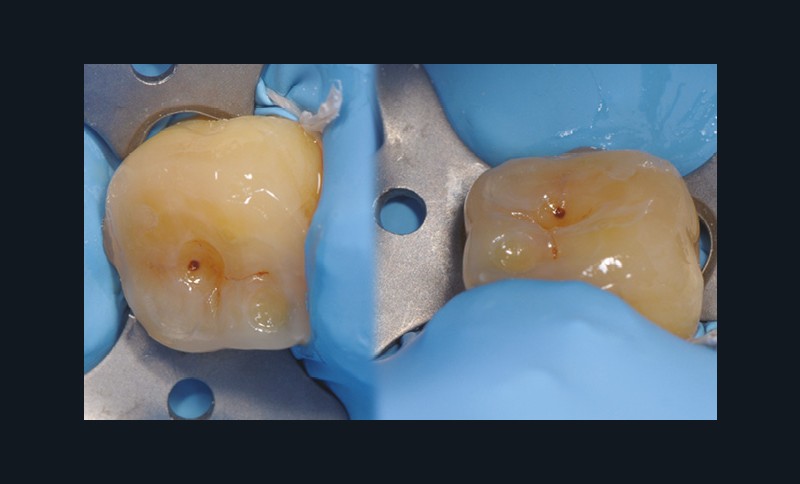

à ces restaurations correspond aujourd’hui toute une série de nouveaux design postérieurs permettant une ultra-préservation tissulaire et pouvant s’inscrire, en fonction des situations cliniques, dans l’émail (situation idéale), dans la dentine, dans le composite de base intermédiaire, ou un « mix » de ces différents supports (fig. 10 à 13).

Les épaisseurs de préparation varient donc selon la nature du support. De 0,6 à 1 mm d’épaisseur sur l’émail jusqu’à 1,5 mm sur la dentine ou le composite afin d’être en adéquation avec les modules d’élasticité des matériaux de restauration utilisés (céramique ou composite).